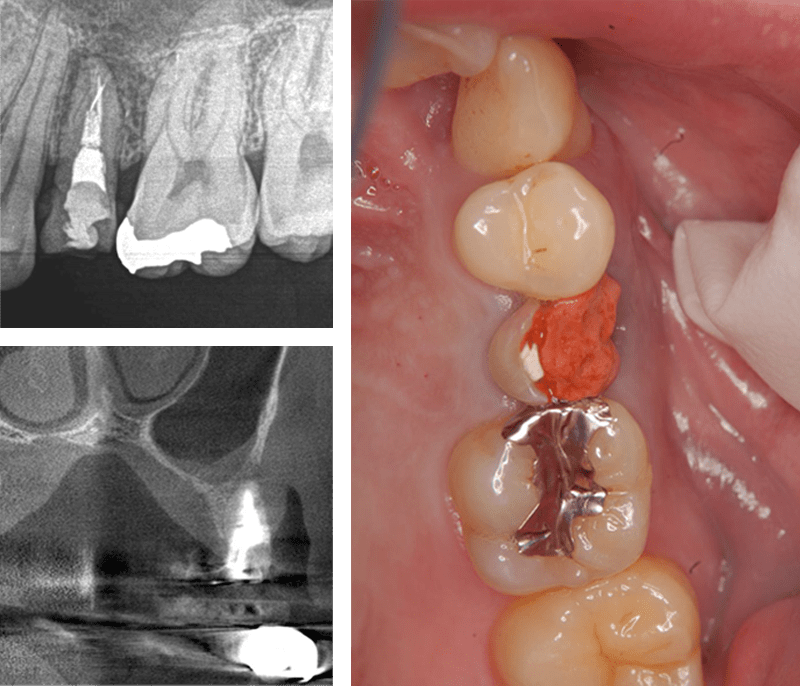

症例3【40代女性】右上74根尖病巣の治療 右上56 洞低膜を挙上しインプラント埋入

治療前

治療後(5年経過)

主訴 右上で物が噛めない。インプラントを希望され来院。

右上第二小臼歯はC₄にて抜歯。右上第一大臼歯は欠損の状態。

残存骨が5~6㎜程で、インプラント埋入には骨の高さが不足している為、ソケットリフト(骨造成)を行った。洞底膜を挙上することで、骨の高さの不足を解消。

採血のよるCGFメンブレンとAFGブロック(人工骨β‐TCPとAFGを混ぜたブロック)を填入しインプラント2本を埋入。約4ヶ月の免荷期間を経て、仮歯を装着、リハビリをし、約5ヶ月後にメタルボンド(金属焼付ポーセレン)を装着。

リスクとしては、ソケットリフト(骨造成)による一過性の副鼻腔炎が起きる可能性がある。まれに洞底膜が破れる可能性がある。ただし、膜は約3週で再生するので、膜の回復を待ち、再オペを行う。

費用 113万(オペ・ソケットリフト・人工骨・採血による濃縮血小板生成・仮歯・最終補綴物まで含む)